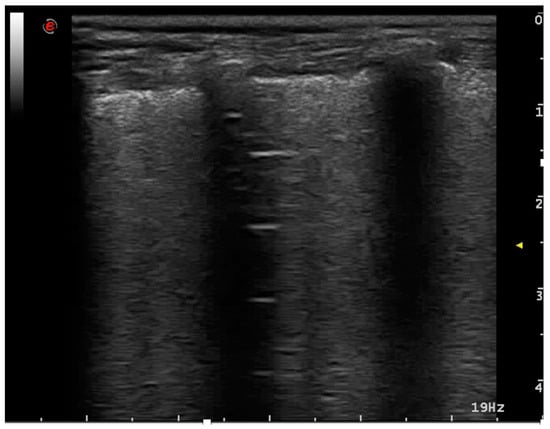

3.2.2. Cardiogenic Pulmonary Edema

- Gargani, L. Lung Ultrasound: A New Tool for the Cardiologist. Cardiovasc. Ultrasound 2011, 9, 1–9. [Google Scholar] [CrossRef] [PubMed]

- Szymczak, J.; Kiełbowicz, Z.; Kinda, W.; Zaleska-Dorobisz, U.; Kubiak, K. Transthoracic lung and pleura ultrasonography as a diagnostic tool of pulmonary edema in dogs and cats. Pol. J. Vet. Sci. 2018, 21, 475–481. [Google Scholar] [CrossRef] [PubMed]

- Rademacher, N.; Pariaut, R.; Pate, J.; Saelinger, C.; Kearney, M.T.; Gaschen, L. Transthoracic lung ultrasound in normal dogs and dogs with cardiogenic pulmonary edema: A pilot study. Vet. Radiol. Ultrasound 2014, 55, 447–452. [Google Scholar] [CrossRef]

- Ward, J.; Lisciandro, G.R.; Keene, B.W.; Tou, S.; DeFrancesco, T.C. Accuracy of point-of-care lung ultrasonography for the diagnosis of cardiogenic pulmonary edema in dogs and cats with acute dyspnea. J. Am. Vet. Med. Assoc. 2017, 250, 666–675. [Google Scholar] [CrossRef]

- Murphy, S.D.; Ward, J.L.; Viall, A.K.; Tropf, M.A.; Walton, R.L.; Fowler, J.L.; Ware, W.A.; DeFrancesco, T.C. Utility of point-of-care lung ultrasound for monitoring cardiogenic pulmonary edema in dogs. J. Vet. Intern. Med. 2021, 35, 68–77. [Google Scholar] [CrossRef]